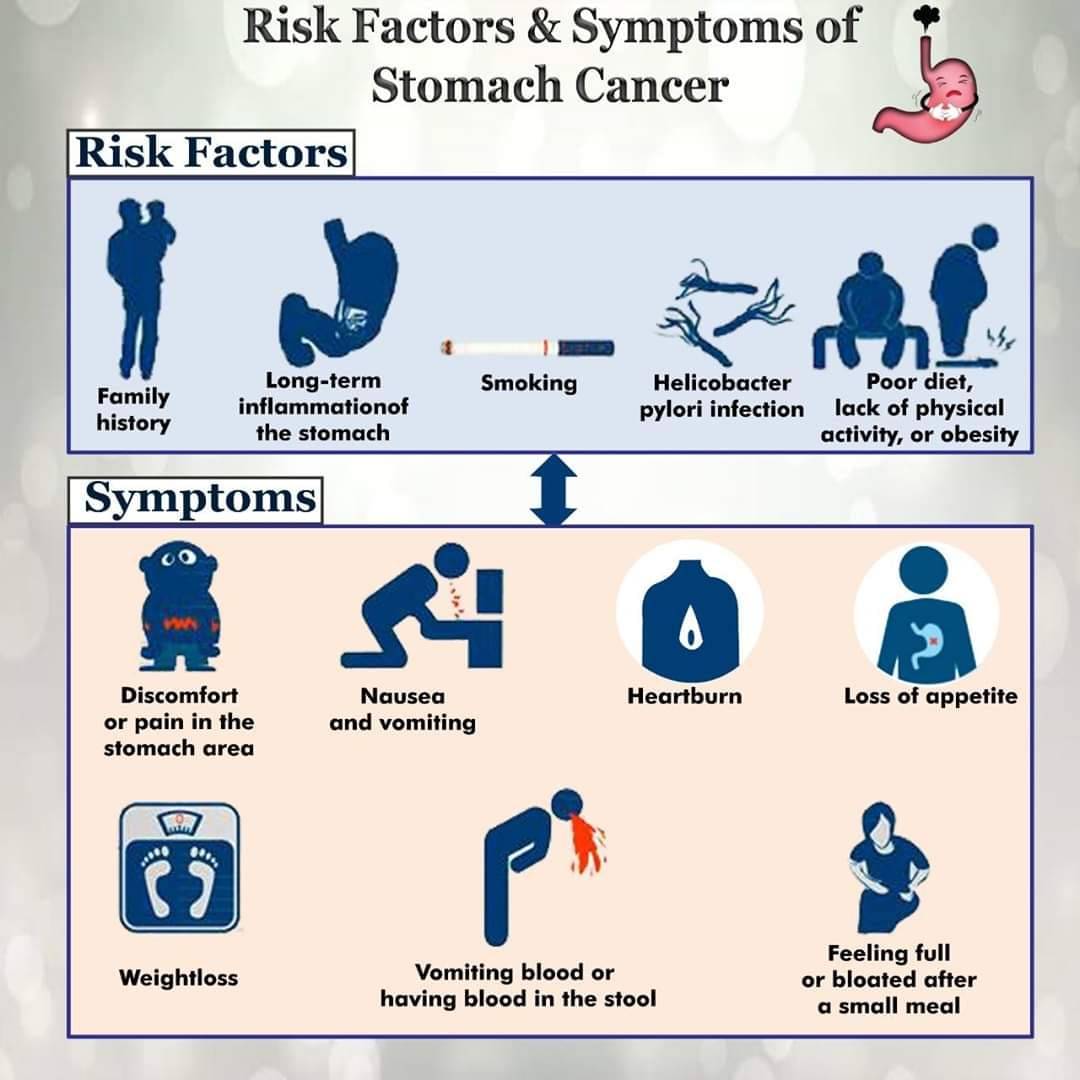

Stomach Cancer – Causes, Symptoms, Diagnosis and Treatment

Stomach Cancer | Symptoms, Causes, Stages, Treatment and Survival Rates

Stomach Cancer | Symptoms, Causes, Stages, Treatment and Survival Rates

How To Prevent Stomach Cancer? | GiDoctor

Cancer in the Stomach|Causes|Symptoms|Stages|Treatment|Survival Rate

Stomach cancer – Mayo Clinic

Symptoms Of Stomach Cancer – Stomach Cancer Symptoms Causes Treatment …

Stomach Cancer Causes and Treatment | Cancer Specialist – Zeeva Clinic

Symptoms Of Stomach Cancer – Stomach Cancer Symptoms Causes Treatment …

What is Stomach Cancer?-Causes, Symptoms, Treatment – Sylvastallone